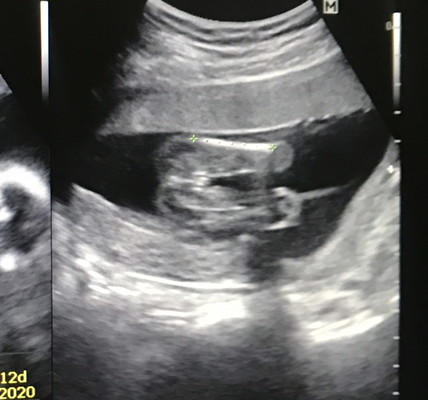

อาหมอบอกอิแม่ว่า 80% เป็นจู๋ ตอนนี้น้องพึ่ง 17w นัตรวจรอบหน้าคงชัดเจน คุณแม่ช่วยดูหน่อยคร๊ะ 😊

ชัดเจนเลยค่ะโชว์อันนี้แต่เอามือบังหน้าไว้ไม่รู้จะเขิลหรืออะไรค่ะ😂

คลอดมาไม่มีทางผิดผลาดเลยค่ะชัดขนาดนี555😂